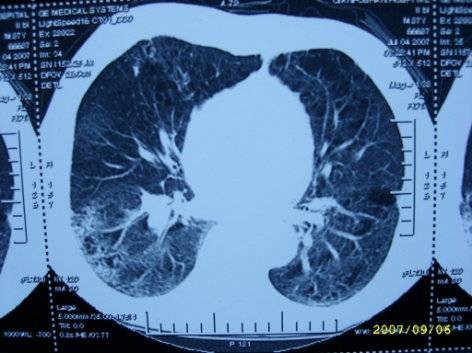

治疗前